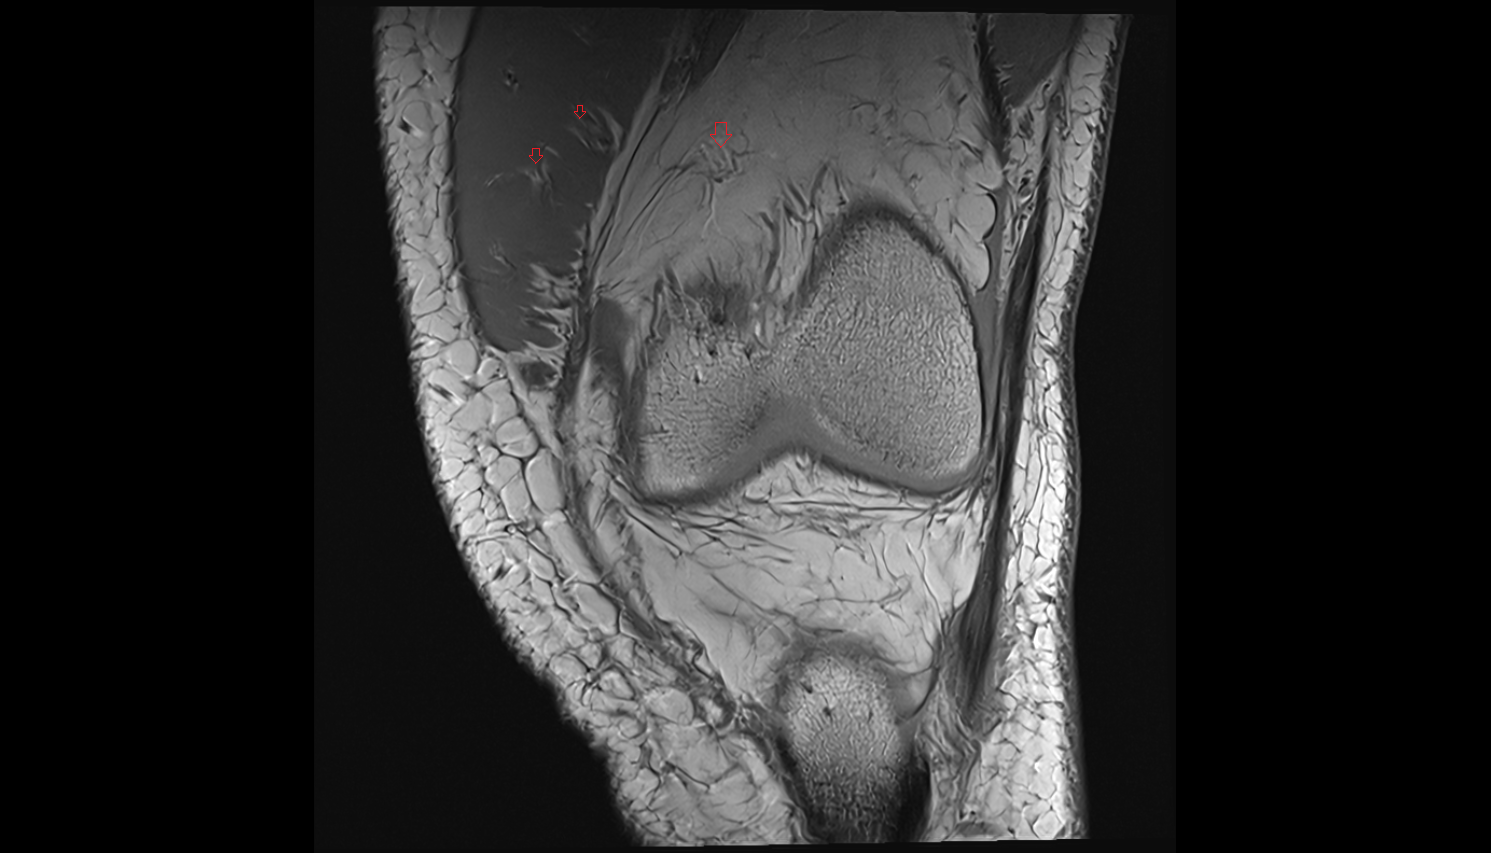

- Knee Joint